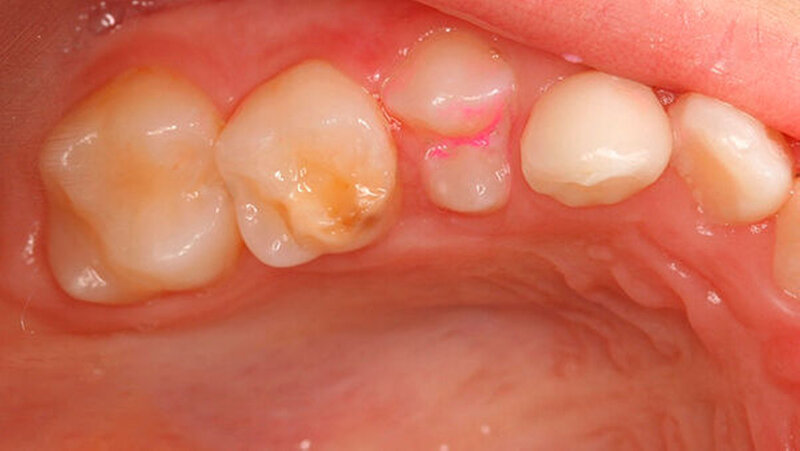

Mit dem Durchbruch der ersten bleibenden Molaren treten dann bisher unbekannte Beschwerden auf wie zum Beispiel eine übermäßig ausgeprägte Kälte-/Wärmeempfindlichkeit. Für manche Kinder wird dadurch nicht nur die Mundhygiene sondern auch die Nahrungsaufnahme erschwert. Zusätzlich bricht oft schon in der Durchbruchs-Phase der Schmelz ein (Abbildung 1), was die Überempfindlichkeit in teils akute Zahnschmerzen übergehen lässt.